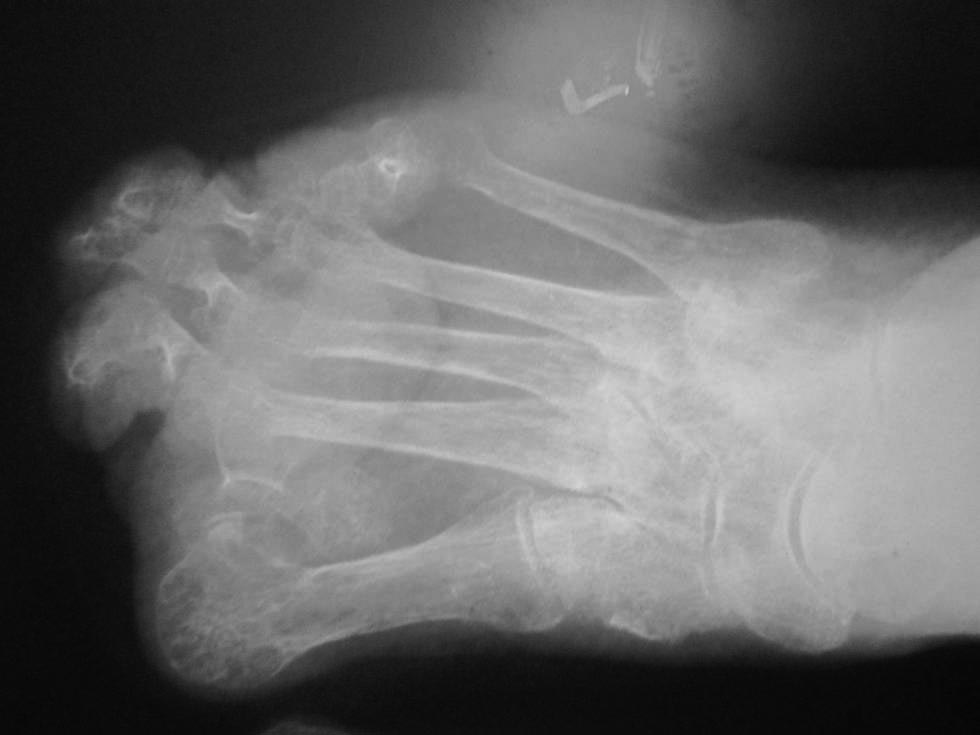

Обратилась больная 75 лет с нallux abductovalgus. начало деформации отмечает с 16 лет. лечение не проводилось.

причина обращения - появление болезненных, длительно незаживающих пролежней на подошвенной поверхности головок 1-х плюсневых костей. Уважаемые коллеги,подскажите пожалуйста план реконструктивной операции.

Случай очень сложный. И по рентгенограмме в одной проекции разобраться невозможно. Как минимум нужна еще одна проекция и фото стопы с тыльной и подошвенной стороны. Ведь по одному снимку неясно, какие пальцы лежат сверху, какие снизу, в каком состоянии сейчас пролежни. А еще лучше - компьютерная томограмма, которая позволит точно понять взаимоотношения фаланг и плюсневых костей, размеры, форму и положение сесамовидных костей.

рентген

Пациентке выполнен артродез 1-ого плюснефалангового сустава, резекции говок 2-3 плюсневых костей, субкапитальная остеотомия 4 плюсневой кости, тенотомиии разгибаталей 2-5 п. стопы. Раны зажили первичным натяжением.